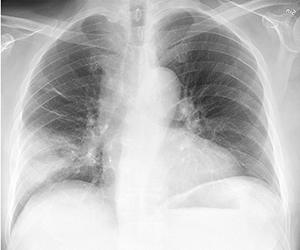

Your doctor would advise Chest X-ray. Based on your symptoms and clinical examination, you may need further test with blood, Sputum or CT scan of chest